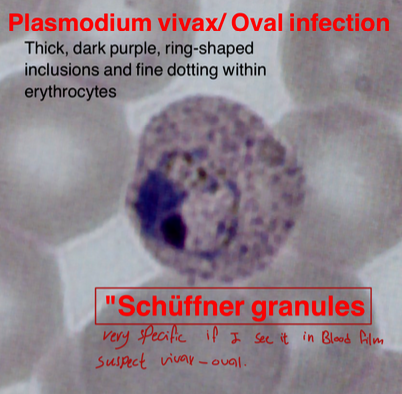

Thick, dark purple, ring-shaped inclusions and fine dotting within erythrocytes.

“Schüffner granules” (very specific if seen in blood film, suspect vivax-oval)

Thick, dark purple, ring-shaped inclusions and fine dotting within erythrocytes.

“Schüffner granules” (very specific if seen in blood film, suspect vivax-oval)

- Name the cause: Vivax - Oval

- Treatment: Primaquine

- What is the specific name? Schüffner granules